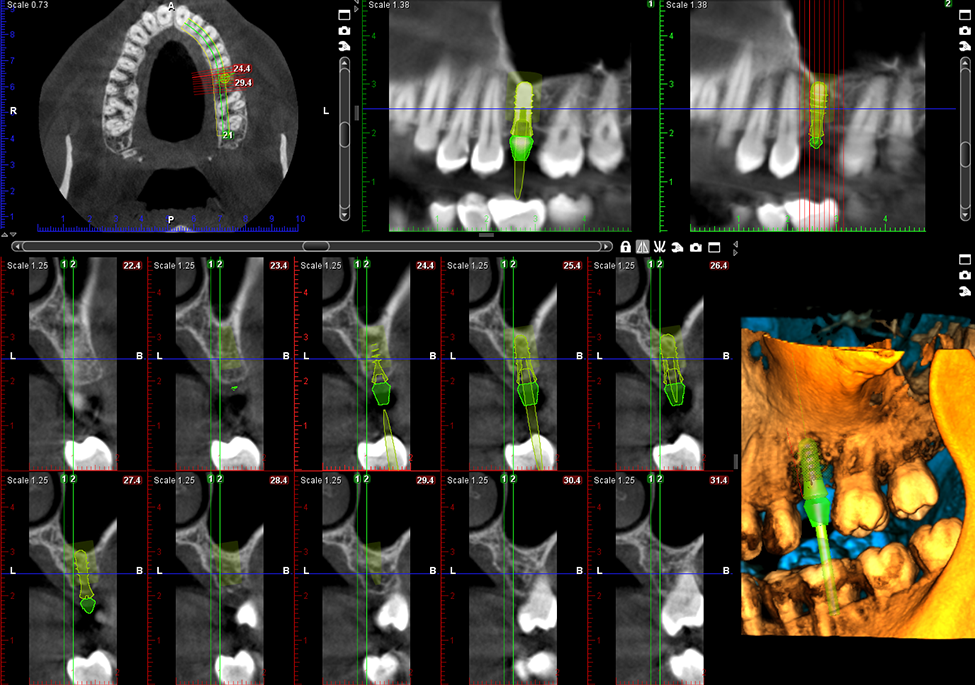

Skanowanie modelu 3D

Skanowanie modeli 3D jest funkcją dostępną dla każdego unitu Planmeca ProMax® 3D. Umożliwia ona skanowanie wycisków i odlewów gipsowych za pomocą jednostki CBCT w celu utworzenia modelu powierzchni bez konieczności użycia skanera wewnątrzustnego. Plik STL modelu powierzchni może być użyty do planowania leczenia.

Obrazy Kliniczne Planmeca ProMax 3D Mid